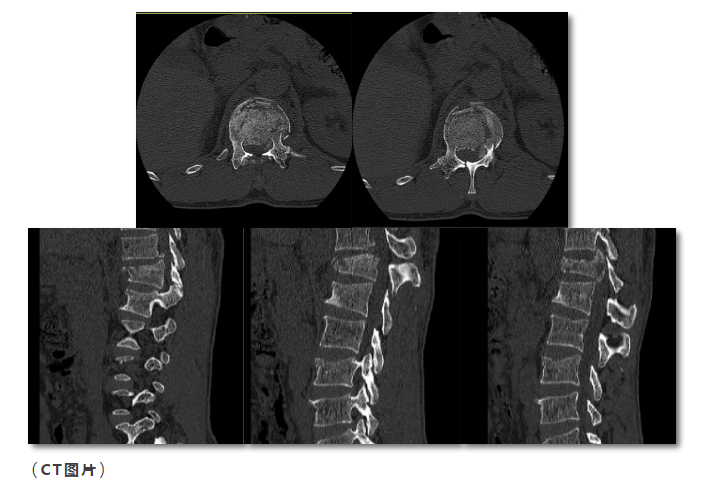

本院2019-07-22胸腰椎CT示:

胸椎第12胸椎压缩爆裂性骨折,骨片分离,椎管有狭窄,两侧附件骨折;第1腰椎轻度压缩性骨折,第1、2腰椎左侧横突骨折。第3腰椎前上缘骨折。

本院腰椎MRI示:

胸12压缩明显,腰1、3椎体上缘轻度压缩骨折,胸12平面脊髓片状高信号。